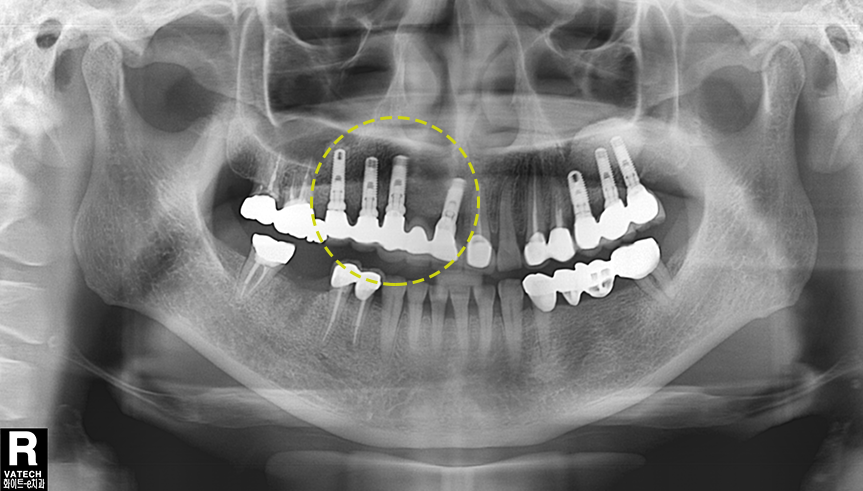

정밀진단과 구강검사

구강 CT촬영, 치아 본뜨기등을 통해 잇몸, 뼈 상태 등을 인접치의 치근, 신경, 혈관 상악동의 위치등에 대한 정보를 면밀히 파악합니다.

치료계획 수립

구강상태에 맞추어 식립 방향과 위치, 깊이, 임플란트의 직경과 길이 등을 결정한 후 수술계획을 수립합니다.

잇몸뼈의 상태 확인

잇몸뼈에 치아 뿌리를 대체할 티타늄을 식립하는 임플란트는 만일 앞니 임플란트를 시술할 부위에 잇몸뼈가 퇴축되어 있다면 앞니 임플란트 최종결과에 심미적 단점을 만들 수 있습니다. 이런 경우 사전에 잇몸뼈 이식 수술을 통해 잇몸뼈를 보강한 후 앞니 임플란트를 시술하면 심미성이 개선될 수 있습니다.